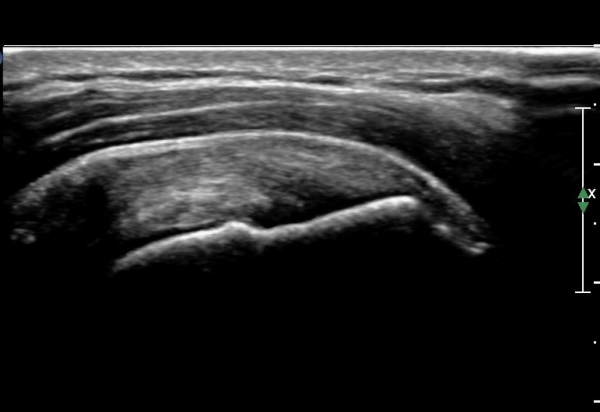

¿À±¸µ¹±â°ßºÀÀδë Á¾´Ü¸é°Ë»ç¿¡¼­ ÀÎ´ë ½ÉÃþ¿¡ ¼ö¾×Àú·ù°¡ °üÂûµÊ(»çÁø 1, 2)

ÀÌ´Â Ãæµ¹ÁõÈıºÀ» ¾Ï½ÃÇÏ´Â ¼Ò°ßÀÓ.